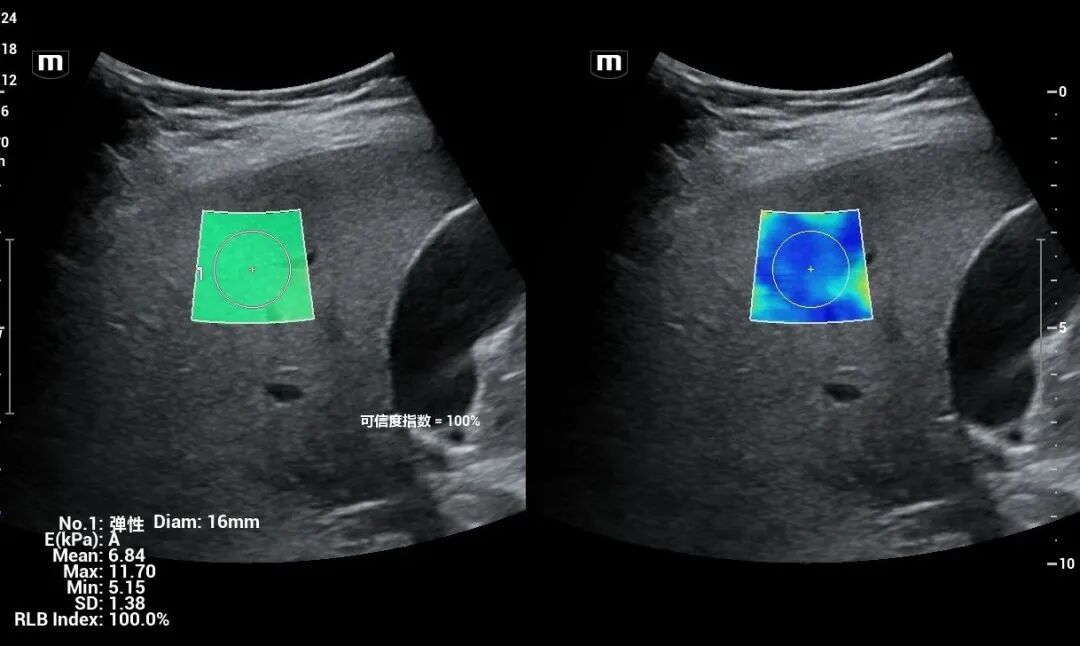

为进一步提高我院诊疗检查与诊断水平,不断满足城乡患者日益增长的就医需求,健全和完善医疗保障体系。2022年12月我院引进了mindray- Resonal9T高端彩色多普勒超声系统正式投入使用,此设备具备超声介入、超声造影、超声高帧率 STE 剪切波弹性成像及应变式弹性成像(甲状腺、乳腺、肝脏),二维、三维、四维、阴式、盆底、心脏及血管超声等功能。此设备的引进标志着海伦影像学科将跨越新的高度,以此助力城乡百姓解决看病难,看病贵的就医难题!

3.体表器官。如乳腺肿物、乳腺增生、甲状腺肿瘤、甲状腺炎。

4.腹部疾病。如腹部脏器肿瘤,肝硬化、胆系结石、泌尿系结石、结核等。